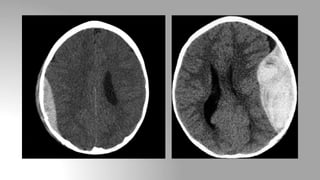

Subdural hemorrhage

• Location: Between the dura and arachnoid mater

• In contrast to EDH, SDH is not limited by sutures but are limited by

dural reflections (falx cerebri, tentorium and falx cerebelli)

• Appearance of SDH depends upon the time since its formation:

Acute SDH (<3 days): Crescentic, hyperdense

Subacute SDH (3-14 days): Nearly isodense, for detection often CECT

is needed

Chronic SDH (>14 days): Hypodense with enhancing membrane.

ACUTE SUBACUTE CHRONIC